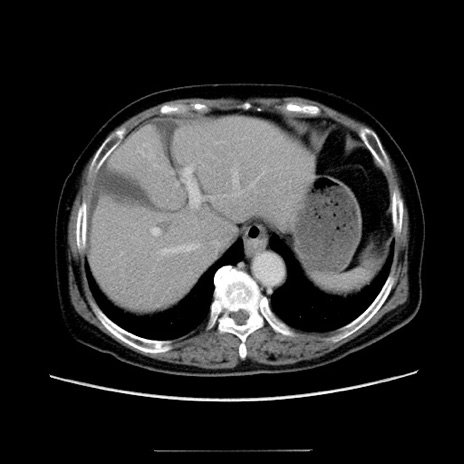

症例5(横断像)

【症例】70歳代女性

【主訴】お腹が張る

【現病歴】1週間くらい前から腹部膨満の自覚あり。昨日夜から増悪したため、本日救急外来受診。

【身体所見】意識清明、BT 36.5℃、BP 165/106mmHg、HR 80bpm、SpO2 98%、腹部:膨満、軟、自発痛・圧痛なし、触診にて不快感あり、腸蠕動音:減弱

【データ】WBC 12600、CRP 1.04